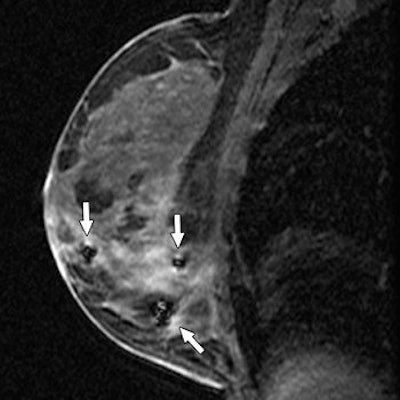

| Same patient as above. Sagittal T1-weighted MR image after needle localization shows signal void from placement of three MRI-compatible bracketing wires (arrows) to assist surgeon in wide excision. Histologic analysis revealed extensive multifocal ductal carcinoma in situ (DCIS), micropapillary, flat (clinging), and focally solid types, intermediate nuclear grade, arising in background of atypical ductal hyperplasia, with multiple positive margins. Mastectomy was performed, yielding residual DCIS with negative sentinel nodes. Lee J, Kaplan JB, Murray MP, Bartella L, Morris EA, Joo S, Dershaw DD, Liberman L, "Imaging-Histologic Discordance at MRI-Guided 9-Gauge Vacuum-Assisted Breast Biopsy" (AJR 2007; 189:852-859). |